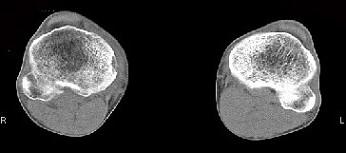

问题 男,38岁,膝关节肿痛,关节弯曲畸形,活动范围受限,胸片示两上肺有斑点状模糊影,请结合所提供的图像,选择最佳选项 ( )

选项 A、膝关节类风湿关节炎 B、膝关节痛风 C、化脓性骨关节炎 D、膝关节退行性变 E、膝关节结核

答案 E